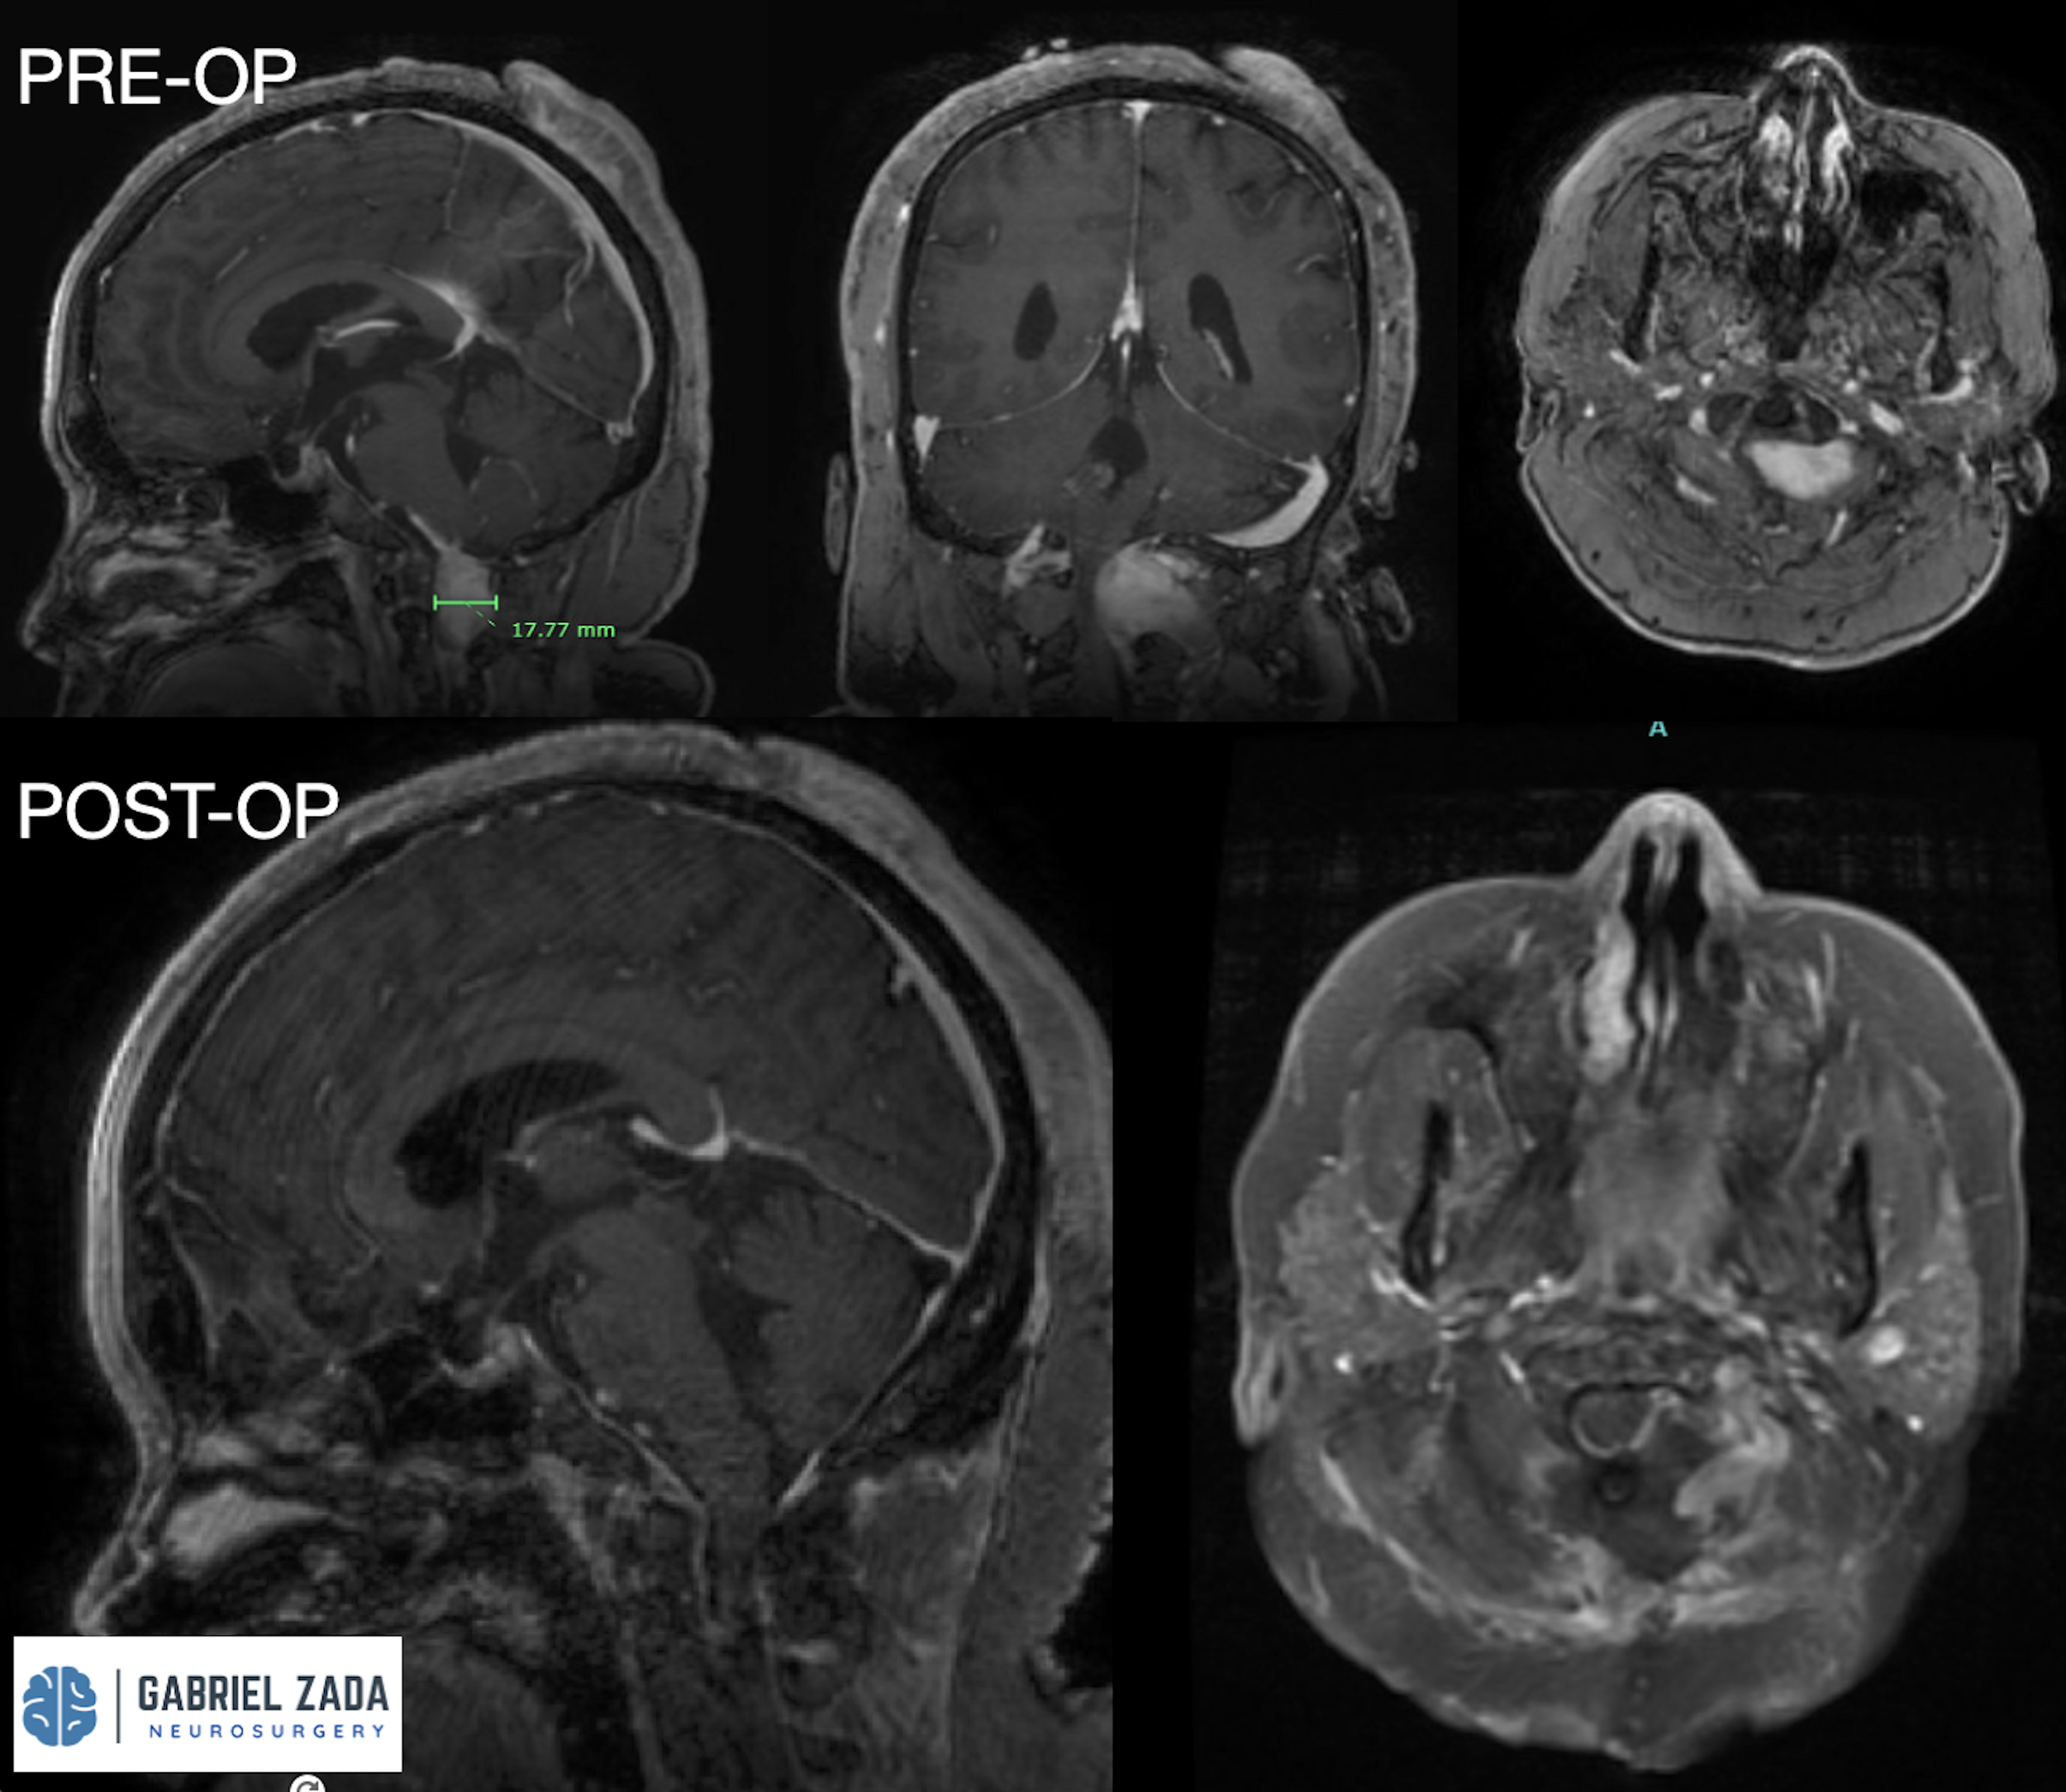

Explore this comprehensive gallery featuring pre‑ and post‑operative imaging of patients with skull‑base tumors treated by Gabriel Zada, MD, MS, FAANS, FACS. These cases highlight Dr. Zada’s expertise in advanced neurosurgical techniques and outcomes.

*Representative cases shown for educational purposes. All images de-identified. Individual results vary.